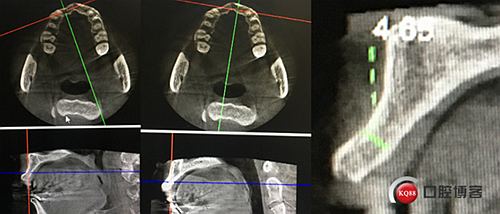

“以修復(fù)為導(dǎo)向”,在前牙種植體中心點(diǎn)就是未來(lái)牙冠舌側(cè)窩位置。那這個(gè)病例植體的方向和位置就只能是下圖右側(cè)這樣了。很明顯植體根尖部分要穿出唇側(cè)倒凹的。怎么辦?翻大瓣植骨蓋膜減張縫合?不!可以不翻瓣,大家仔細(xì)看看下圖右圖我畫(huà)的那條細(xì)細(xì)的弧線,是不是跟原來(lái)唇側(cè)凹陷的骨面成為左右對(duì)稱的兩條弧,也就是說(shuō)骨膜從原來(lái)唇側(cè)凹陷骨面上剝離然后放到左側(cè)我畫(huà)的那條弧線那里根本不需要減張,這兩條弧線之間也就是唇側(cè)凹陷處放上骨粉,骨膜不會(huì)增加張力。不知道大家看明白了沒(méi)有。